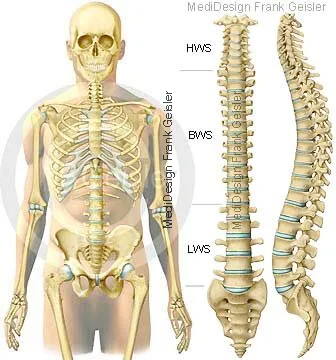

Das Skelett (Skeletos) ist eine Stützstruktur im Inneren des Körpers, es besteht aus etwa 206 Knochen und wird in einen axialen und einen Extremitätenteil unterschieden. Das menschliche Skelett braucht mehrere Jahre, bis es vollständig entwickelt ist. Obwohl der Oberarmknochen (Humerus) bereits im Mutterleib (8. Woche) verknöchert (ossifiziert), ist das Skelett erst um das 20. Lebensjahr herum vollständig entwickelt.

Das menschliche Skelett gliedert sich in die Knochen des Stammes und der Extremitäten. Das Stammskelett umfasst die Knochen des Kopfes und des Rumpfes, während das Skelett der Extremitäten aus den Knochen vom Schultergürtel und Beckengürtel und denen der freien Teile der oberen und unteren Extremität besteht

Körper mit Skelett, Darstellungen der Wirbelsäule; Lamellenknochen mit Knochenmark; Knochengewebe mit Osteoblasten und Osteozyten

Das Rumpfskelett wird von Wirbel (Vertebrae), Rippen (Costae) und dem Brustbein (Sternum) gebildet. Das Skelett besitzt Stützfunktionen für den Rumpf und die Extremitäten, liefert Ursprungsstellen und Ansatzstellen für die Skelettmuskulatur und Gelenkkörper für seine Beweglichkeit. Die Schädelknochen umgeben schützend das Gehirn, die Wirbel das Rückenmark, der Brustkorb bildet einen Schutz für die Brustorgane und das Becken für die Beckeneingeweide. In den Markhöhlen im Innern der Knochen befindet sich das Knochenmark. Die Anzahl der das Skelett bildenden Knochen verändert sich während des Lebens. Einige, die ursprünglich getrennt angelegt werden, vereinigen sich im Verlauf der Skelettentwicklung miteinander.

Im mittleren Lebensalter besteht das Skelett eines Menschen aus mehr als 200 einzelnen Knochen. Die Wirbelsäule (Columna vertebralis) setzt sich aus 24 Wirbeln (Vertebrae), dem Kreuzbein (Os sacrum) und dem Steißbein (Os coccygis) zusammen. Das Kreuzbein bildet sich durch die Verschmelzung von fünf einzelnen Wirbeln, das Steißbein entsteht aus zwei bis sieben Wirbelrudimenten. Zum Stammskelett gehören außerdem das Brustbein (Sternum) und die zwölf Rippenpaare (Costae). Das Kopfskelett, der Schädel (Cranium), besteht insgesamt aus 33 einzelnen Knochen, davon werden 15 dem Hirnschädel und 18 dem Gesichtsschädel zugeordnet. Zum Schultergürtel gehören jeweils rechts und links das Schlüsselbein (Clavicula) und das Schulterblatt (Scapula). Die obere Extremität wird gebildet vom Oberarmbein (Humerus), der Speiche (Radius), der Elle (Ulna), acht Handwurzelknochen (Ossa carpi), fünf Mittelhandknochen (Ossa metacarpalia I-V) und vierzehn Fingerknochen (Ossa digitorum manus).